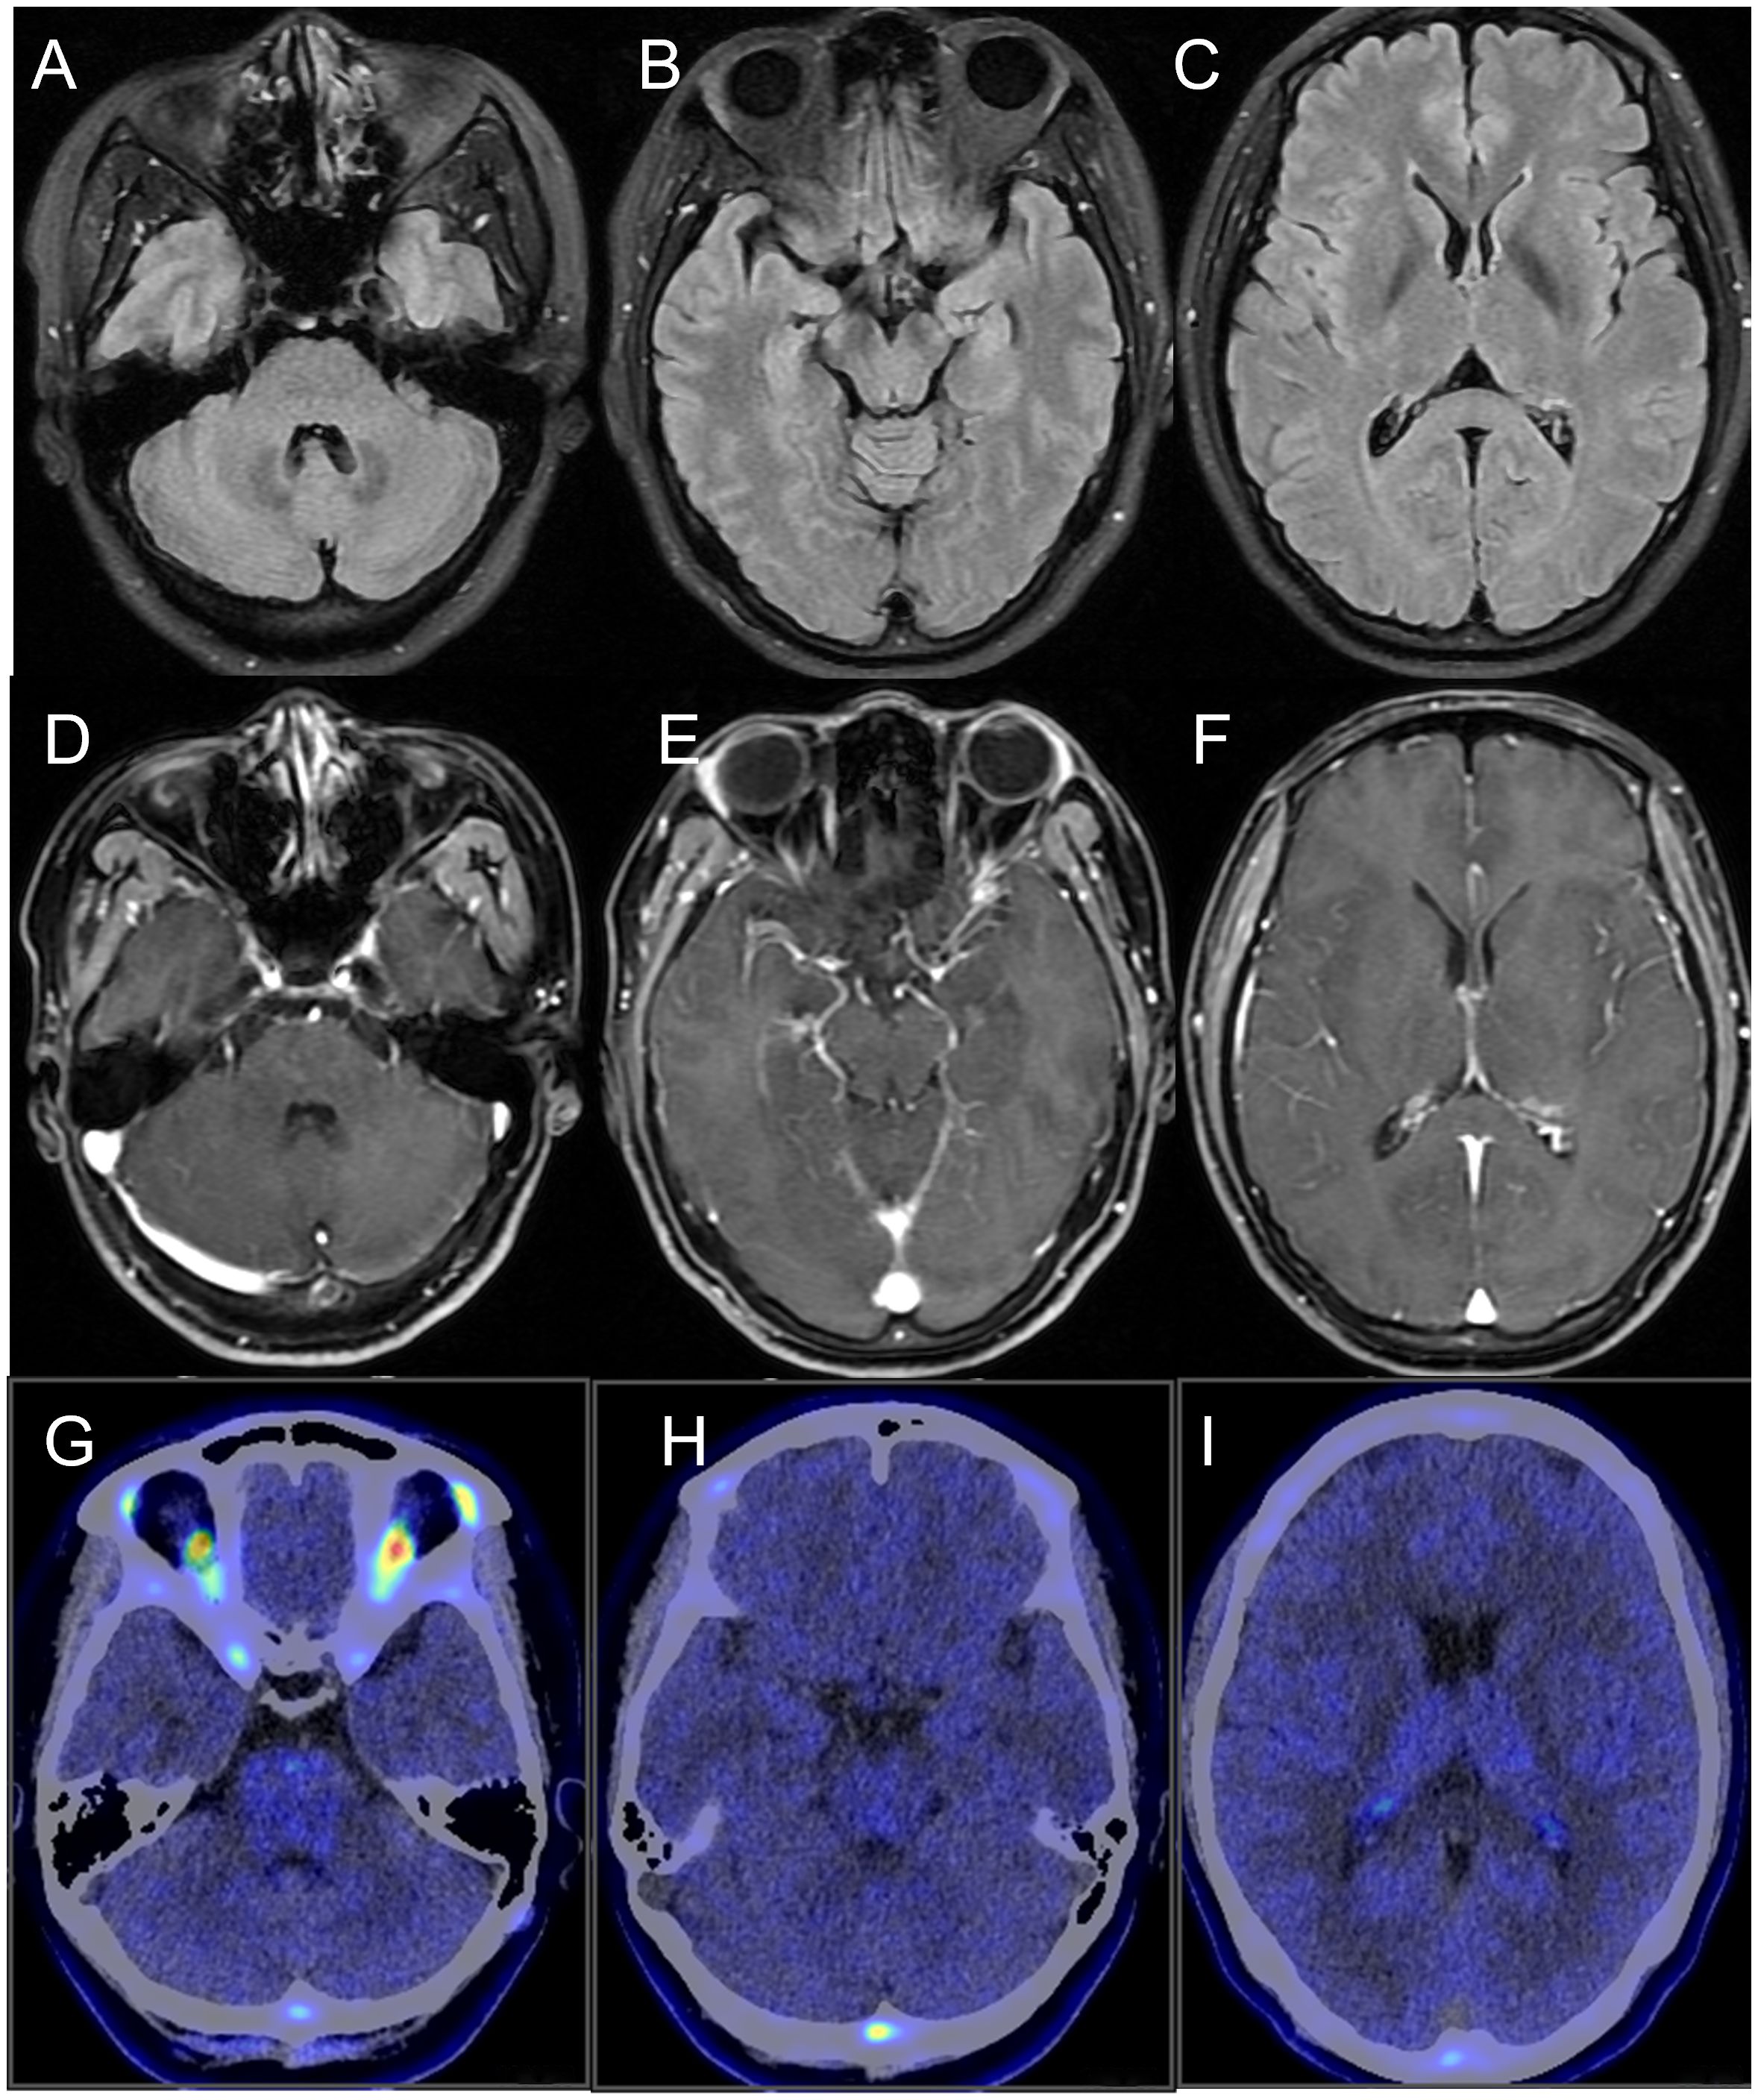

Kelch-like protein 11 (KLHL11) encephalitis is a rare clinical condition characterized by autoimmune-mediated encephalitis associated with the presence of KLHL11 antibodies, which commonly presents with ataxia, diplopia, vertigo, hearing loss, and seizures. While the link between this high-risk paraneoplastic autoantibody and male testicular germ cell tumors is well-established, female cases are rare, and no case of ductal breast carcinoma or dual primary malignancies have been reported. The disease is generally resistant to conventional therapies. In this study, we reported a case of KLHL11 encephalitis in a female patient presenting with fever, seizures, and ataxia, alongside dual primary malignancies: ductal breast carcinoma and pulmonary adenocarcinoma. Following immunotherapy with a neonatal Fc receptor (FcRn) inhibitor (efgartigimod) and resection of tumors, the patient achieved complete symptomatic remission with no recurrence. Current studies showed that KLHL11 encephalitis contributed to pathogenesis through cytotoxic T-cell-mediated neuronal injury and loss. However, in this case, rapid clinical improvement was observed after FcRn inhibitor therapy. This is the first report of FcRn inhibitor in the treatment of KLHL11 encephalitis. This case demonstrated a rare association of KLHL11 encephalitis with breast and lung cancer, and expanded on the clinical manifestations, associated tumor types, and treatment options of KLHL11 encephalitis in women.